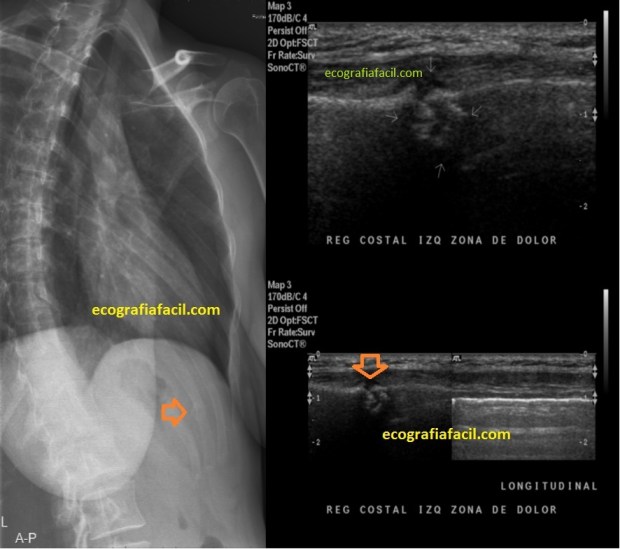

Las fracturas costales, a veces muy difíciles de ver con RX, podemos verlas en ecografía, como en esta imagen donde puedes ver costilla normal, lineal e hiperecogénica y a su lado la fractura en una costilla rota y su representación sobre la placa, prácticamente inapreciable.

The rib fractures, sometimes very difficult to see with RX, we can see them in ultrasound, as in this image where you can see normal, linear and hyperechoic rib and next to it the fracture in a broken rib and its representation on the plate, practically inappreciable.